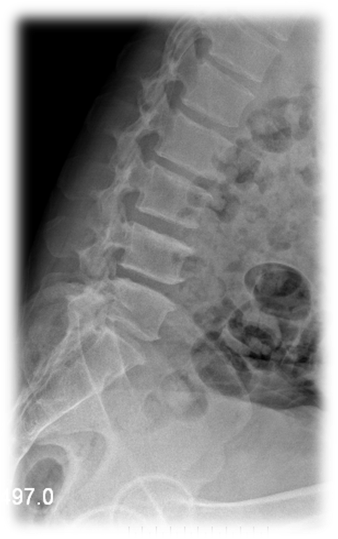

术前 图片3